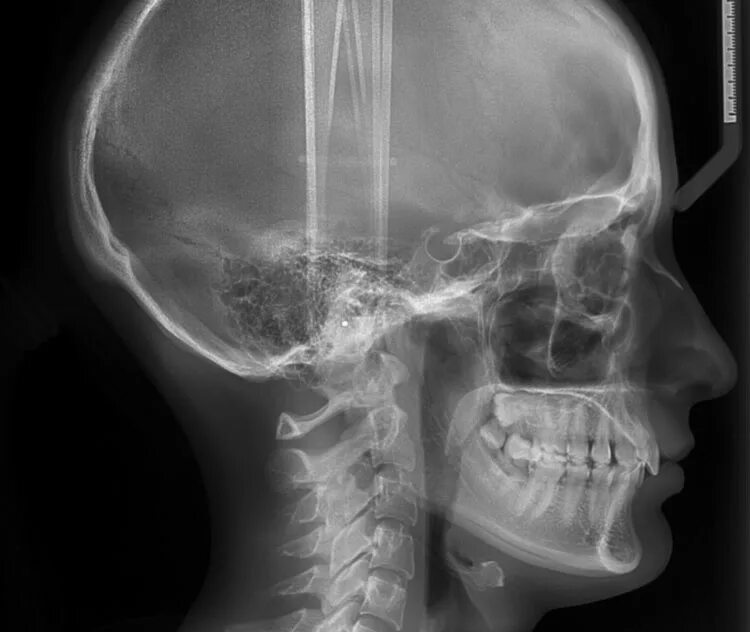

Проекции рентгенограмм черепа